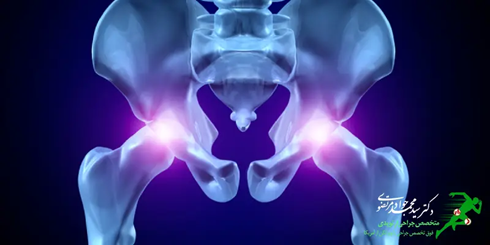

درمان شکستگی لگن

لگن عضو مهمی در بدن است که به شکل حلقوی بوده و در قسمت تحتانی بدن قرار دارد. این عضو به عنوان کانال ارتباطی بین اندام های پایین بدن با تنه بوده و از قسمت فوقانی به ستون فقرات و از قسمت تحتانی به استخوان های ران متصل می باشد. نقش لگن انتقال نیروهای وارد شده از تنه به اندام های قسمت تحتانی بدن می باشد. اعضای گوارشی و تولید مثل، عروق و بافت های عصبی مهم در قسمت تحتانی بدن از لگن عبور می کند. در صورتی که استخوان این عضو دچار آسیب شود فرد متحمل درد زیادی می شود که برای درمان شکستگی لگن بایستی به متخصص ارتوپدی مراجعه نمایید. از شایعترین آسیب های لگن، شکستگی لگن است.